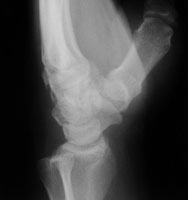

- Click on the image for a larger versionBOblique radiograph of the wrist. This shows a fracture of the body of the hamate.